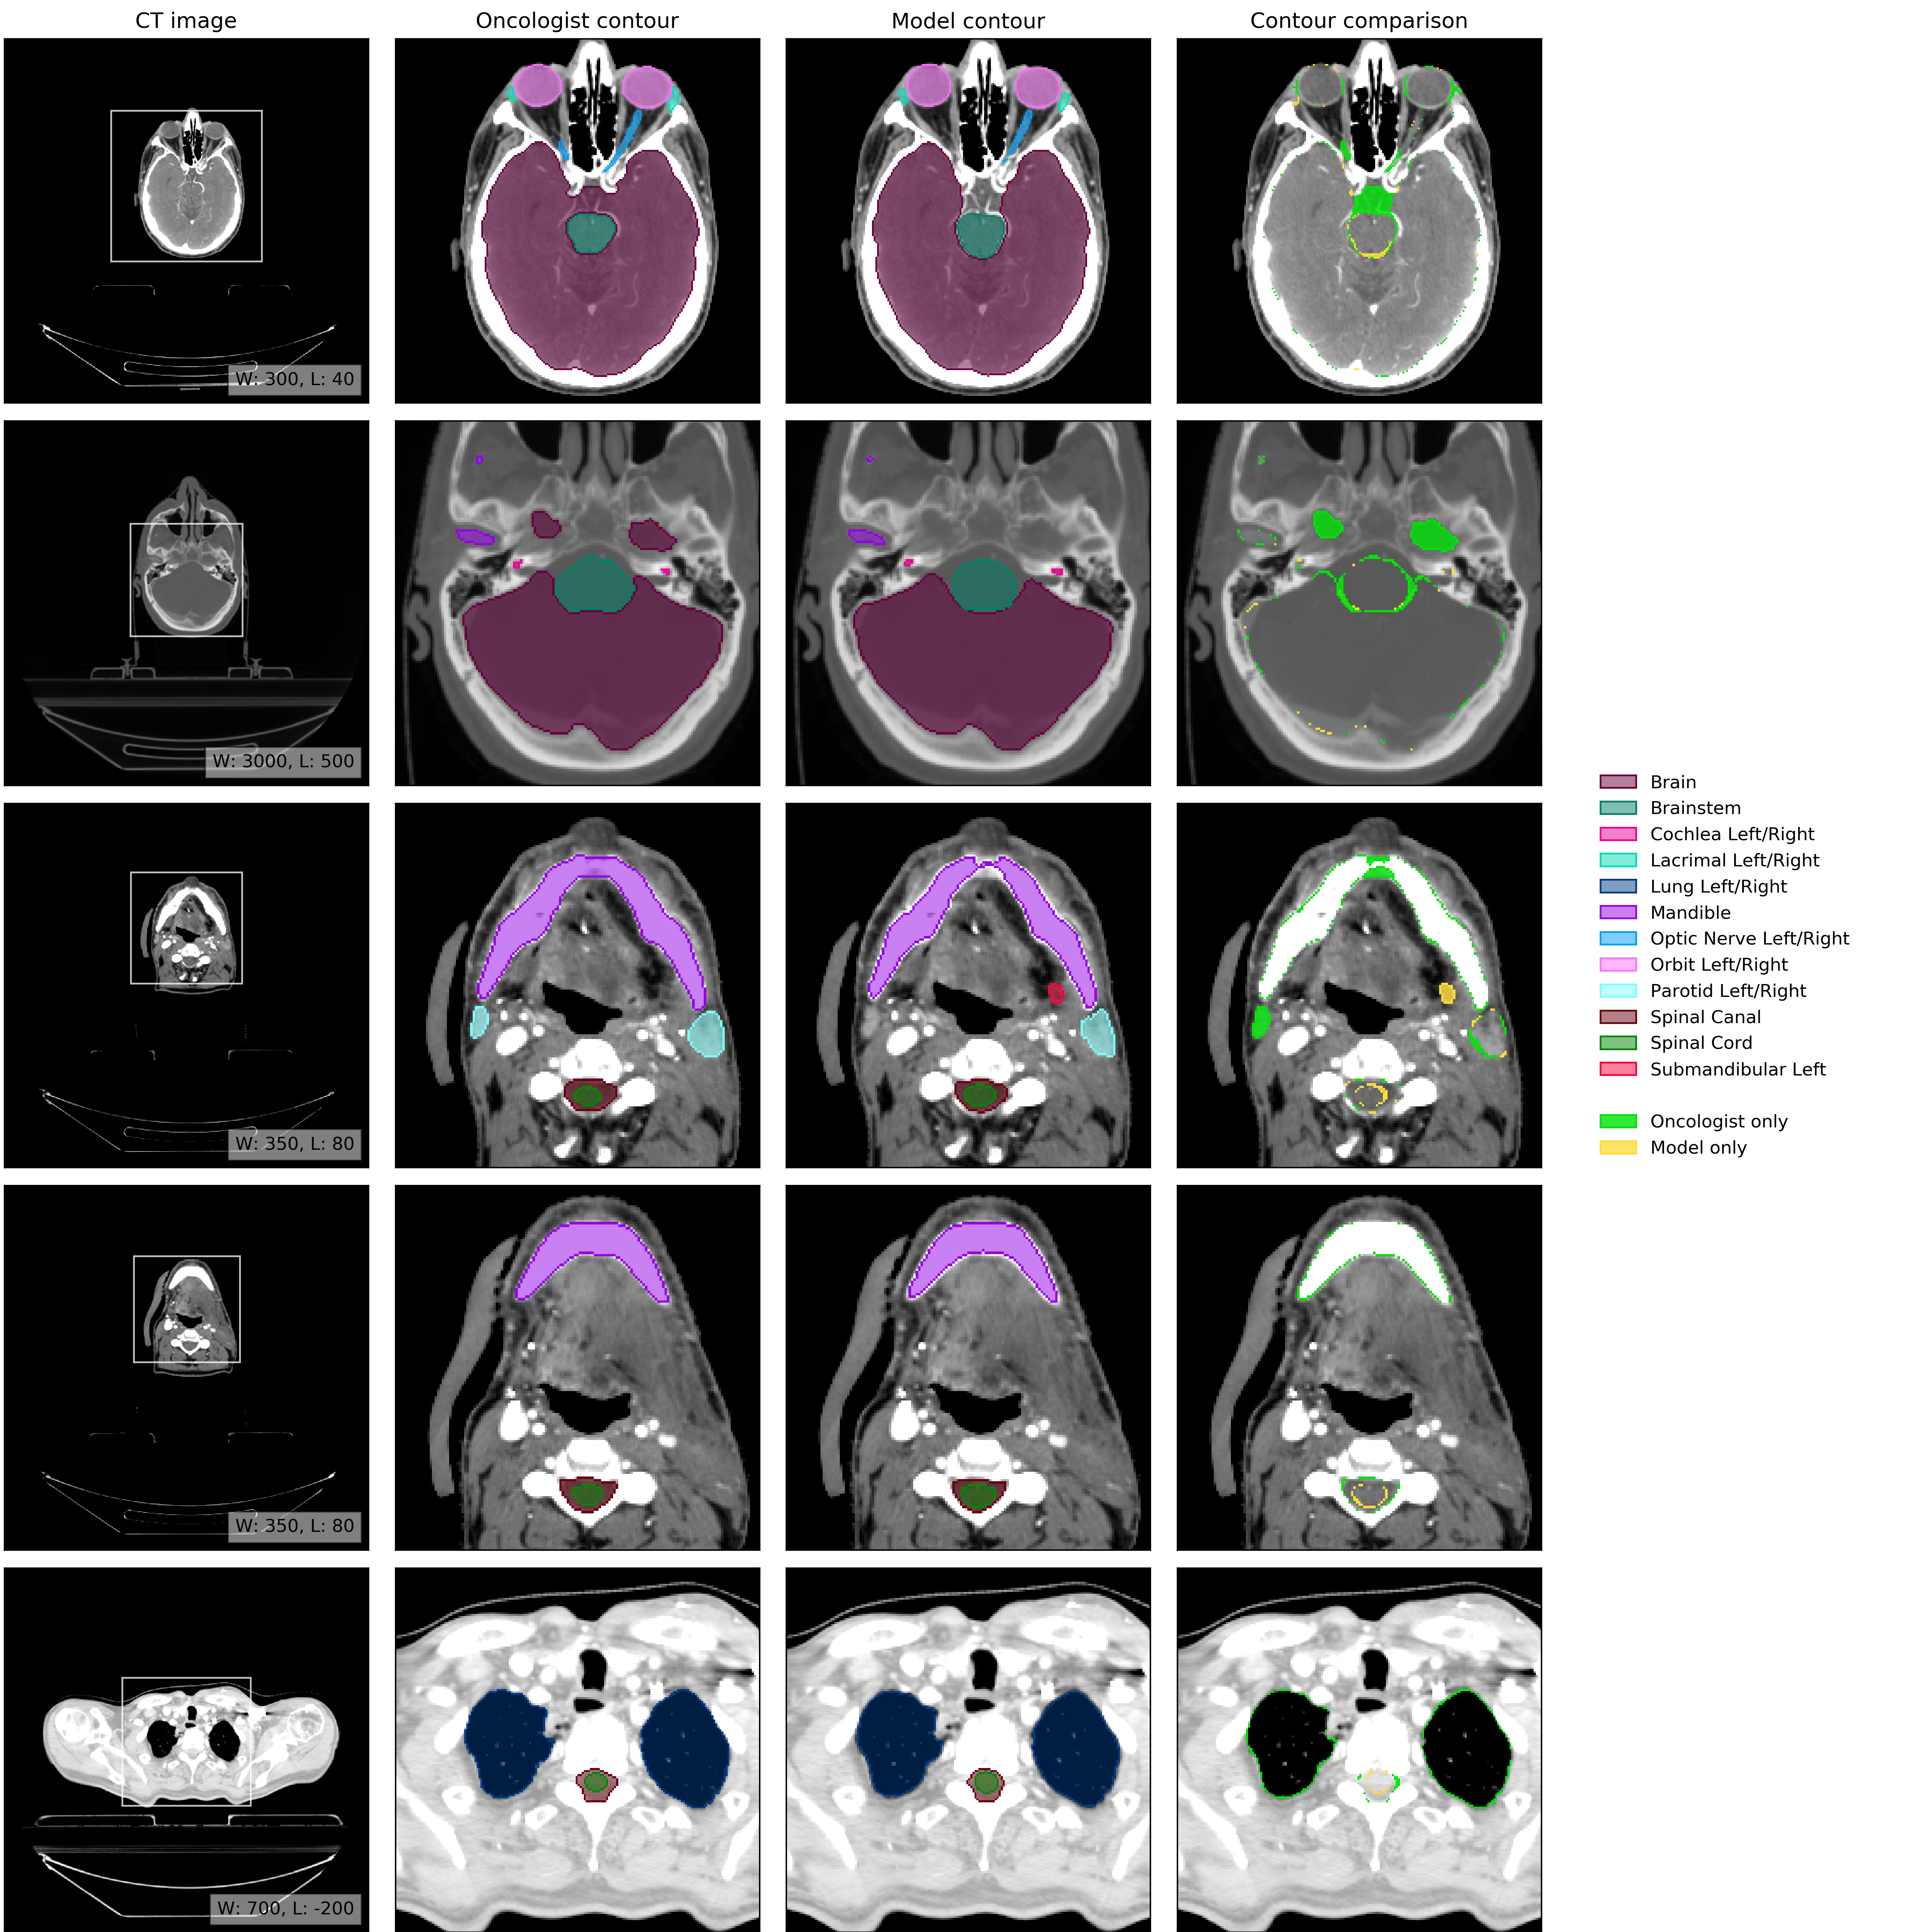

An example of model performance is shown in Fig. 2. We compare our performance (model vs oncologist) to radiographer performance (radiographer vs oncologist). For more information on dataset selection, inclusion and exclusion criteria for patients and OARs please refer to the Methods section.

Refer to caption

Figure 2: Example results. (CT image) Axial slices at five representative levels from the raw CT scan of a 55-59 year old male patient was selected from the UCLH dataset (patient UCLH-20) were selected to best demonstrate the OARs included in the work. The levels shown as 2D slices have been selected to demonstrate all 21 OARs included in this study. The window levelling has been adjusted for each to best display the anatomy present. (Oncologist contour) The ground truth segmentation, as defined by experienced radiographers and arbitrated by a head and neck specialist oncologist. (Model contour) Segmentations produced by our model. (Contour comparison) Contoured by Oncologist only (green region) or Model only (yellow region). Two further randomly selected UCLH set scans are shown in Fig. 12 and Fig. 13. Best viewed on a display.